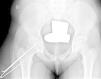

Diagnóstico por la imagenLas radiografías anteroposterior y axial de ambas caderas nos permitirán confirmar el diagnóstico. Es importante obtener la radiografía de ambas caderas por la alta incidencia de bilateralidad. En la radiografía antero-posterior y axial de ambas caderas podemos observar un desplazamiento antero-superior de la metáfisis proximal del fémur (cuello femoral) respecto a la epífisis (cabeza femoral). Denominamos signo de Steel, a la doble densidad radiográfica creada por la epífisis que se desplaza posteriormente y se superpone a la parte medial de la metáfisis (fig. 1). La línea de Klein, es una línea que se traza en la parte antero-superior del cuello femoral en la radiografía antero-posterior y que corta la epífisis. En los casos de ECF, la epífisis femoral queda por debajo de esta línea (fig. 2).